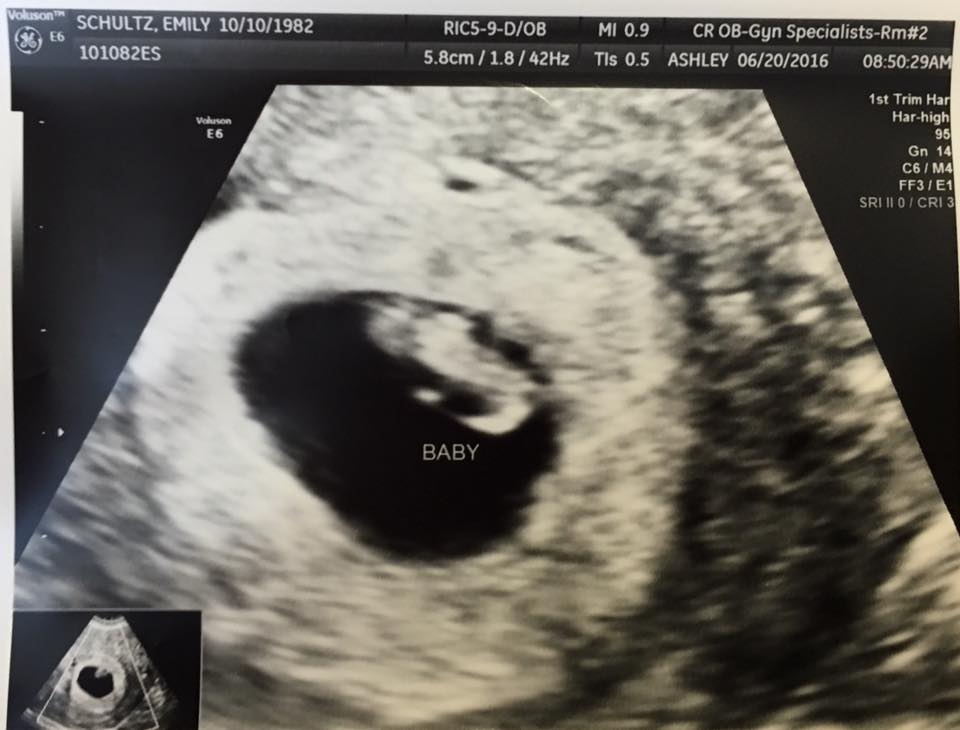

Anyone good at Ramzi method?? I have had four scans this pregnancy so far due to a SCH at 6, 7, 8, and today at 9+2. Just wondering your thoughts on this method, I know it's early and not 100% ;-)

Attachment 32033Attachment 32034Attachment 32035Attachment 32036